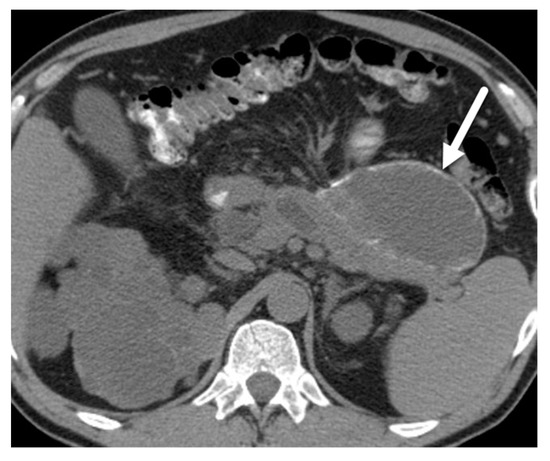

- Macari, M.; Finn, M.E.; Bennett, G.L.; Cho, K.C.; Newman, E.; Hajdu, C.H.; Babb, J.S. Differentiating pancreatic cystic neoplasms from pancreatic pseudocysts at MR imaging: Value of perceived internal debris. Radiology 2009, 251, 77–84. [Google Scholar] [CrossRef]

- Tirkes, T.; Aisen, A.M.; Cramer, H.M.; Zyromski, N.J.; Sandrasegaran, K.; Akisik, F. Cystic neoplasms of the pancreas; findings on magnetic resonance imaging with pathological, surgical, and clinical correlation. Abdom. Imaging 2014, 39, 1088–1101. [Google Scholar] [CrossRef] [PubMed]